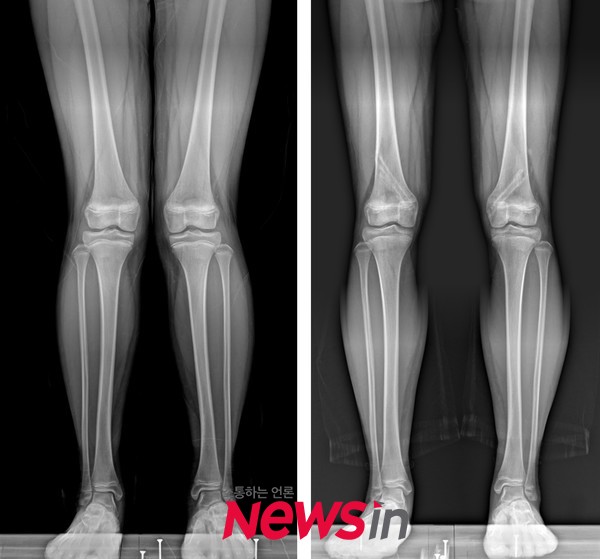

[뉴스인] 조진성 기자 = 소아 환자에서 엑스(X)자 다리 교정 수술 후 재발뿐 아니라 과교정 또한 주의해야 한다는 연구 결과가 발표되었다.

하지만 인제대학교 해운대백병원 정형외과 박병규 교수와 세브란스 어린이병원 소아정형외과 박건보 교수팀이 공동으로 시행한 연구에 따르면 금속 기구의 제거 이후에도 교정의 효과가 유지되지 않고 다리의 모양이 계속 변화하여 재발 또는 과교정이 발생할 수 있는 것으로 나타났다.

그 결과 53%에서는 교정의 효과가 유지되었지만, 나머지에서는 교정 후 다리 모양이 유지되지 않고 재발 또는 과교정을 나타내었다. 성장판 기능의 억제를 위해 나사못을 사용하였을 때 금속판에 비해 짧은 교정 기간과 빠른 교정 속도를 보여주었다. 하지만 금속 제거 후에도 허벅지뼈에서 교정이 지속되어 과교정의 위험이 컸다. 반면에 금속판을 사용하였을 때는 허벅지뼈에서 변형이 재발되는 경향이 나타났다. 정강이뼈는 나사못과 금속판에 상관없이 제거 후에도 유의미한 변화를 보이지 않았다.